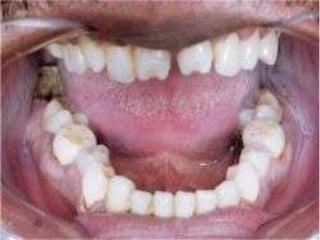

Acute ulcerative	SyphilisCongenital syphilisHutchinson’s incisors, “moon’s molars”	Primary		painless, indurated, ulcerated, usually involving the lips, tongue	Secondary- mucous patches, split papules	Tertiary- Gummas, can involve palate, tongue